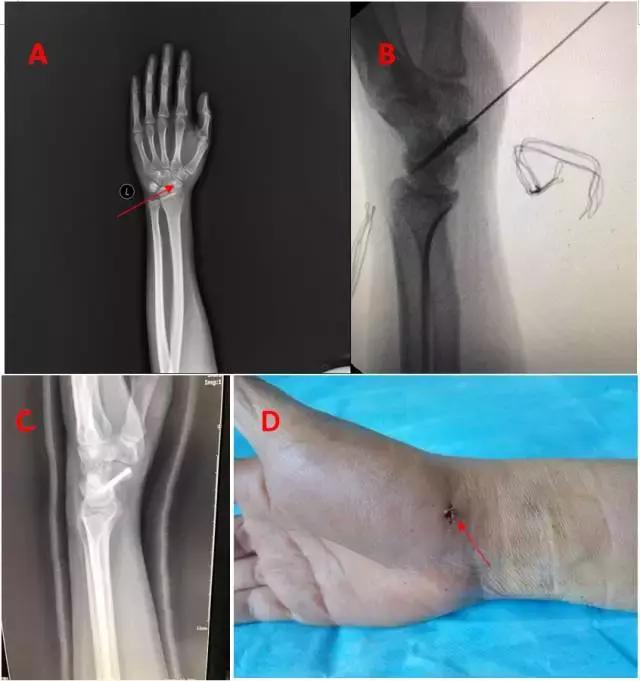

患者张某,因跌倒致左腕部肿痛,功能障碍7天入院治疗。检查发现患者左腕部肿痛,功能障碍,环形叩痛,纵扣痛,自主活动受限,手指还可活动。左腕部正侧位拍片发现左腕舟骨骨折。根据患者情况,骨伤科一病区采用了经皮Herbert螺钉内固定治疗腕舟骨骨折,术后效果明显。

图A:箭头所示,术前见腕舟骨骨折;

图B:术中克氏针引导植入Herbert螺钉;

图C:术后复查见腕舟骨固定良好;

图D:术后拆线,见切口愈合,瘢痕小,美观。